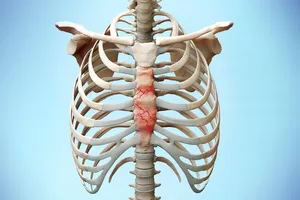

12. 갈비뼈 골절

갈비뼈는 우리 몸의 중요한 내장기관을 보호하는 울타리와 같은 역할을 합니다. 하지만 강한 충격이나 외상으로 인해 갈비뼈가 부러지면, 마치 울타리가 무너진 것처럼 흉통이 심해질 수 있습니다. 특히 숨을 쉴 때나 기침을 할 때, 그리고 부러진 부위를 누를 때 통증이 더욱 악화되는 것이 특징입니다. 따라서 가슴에 강한 충격을 받은 후 심한 통증이 지속된다면, 정확한 진단을 위해 병원에서 X-ray 검사 등을 받아보는 것이 좋습니다.